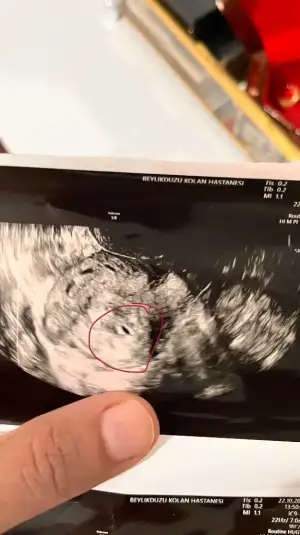

Merhabalar kızlar benim de son adet tarihim 17 Eylül . Bugün keseyi görmek için hastaneye gittim. Doktor keseyi gördü ama net bir şey demedi . Elime de saçma sapan bir ultrason fotoğrafı sıkıştırdı . Neyin ne olduğu belli değil. 3 bin lira da muayene ücreti verdim . Sinirim aşırı bozuldu. Her ihtimal olabilir diyor .

Şu gebelik kesesi . Siz ne düşünüyorsunuz. Pişman oldum o kadına gittiğime . Net bir şey söylemedi . Dış gebelik olsa anlaşılmaz mı ya . Bunlar nasıl doktor ???